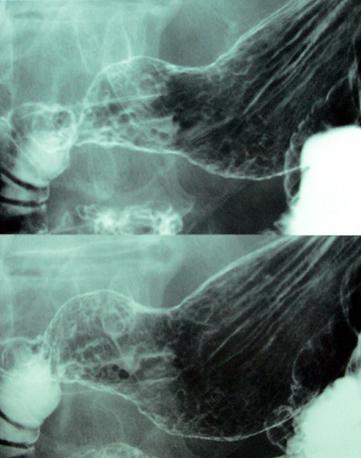

clasificación del pacienteTumor Maligno del Sistema Linfático/Linfoma Maligno

parte(separada por órganos)estómago(región)/antro

método de exámenRayos X

clasificación ectoscópica de tumoresTipo 0(tipo superficial)/Tipo IIc(IIc)

diámetro mayor del tumor40 -

grado de penetraciónsm